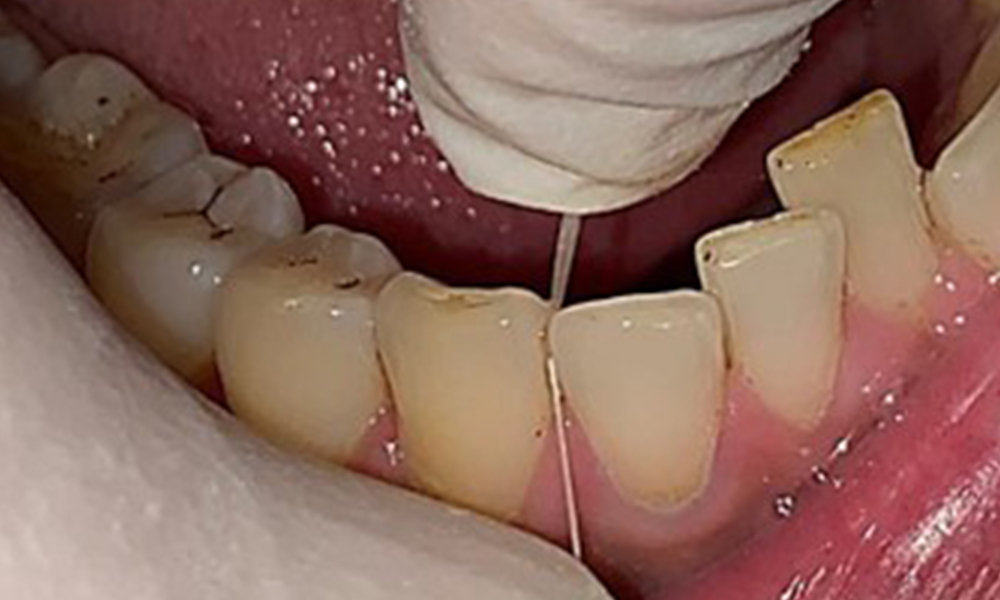

Discolouration caused by nicotine and tea consumption can be removed easily using an air polisher (Fig. 11).

Air polishing system use in the mandibular frontal lingual area (here, Proxeo Aura, W&H)

Fig. 11 Air polishing system use in the mandibular frontal lingual area (here, Proxeo Aura, W&H), © Dr R. Krapf

When using more abrasive powder, it is essential to work from a cervical to coronal direction and never point the outlet nozzle towards the gingiva to prevent potential emphysema. Good suction on the contralateral side is essential to reduce aerosol formation (Fig. 12).

Use of the air polishing system away from the sulcus with contralateral suction.

Fig. 12 Use of the air polishing system away from the sulcus with contralateral suction, © Dr R. Krapf